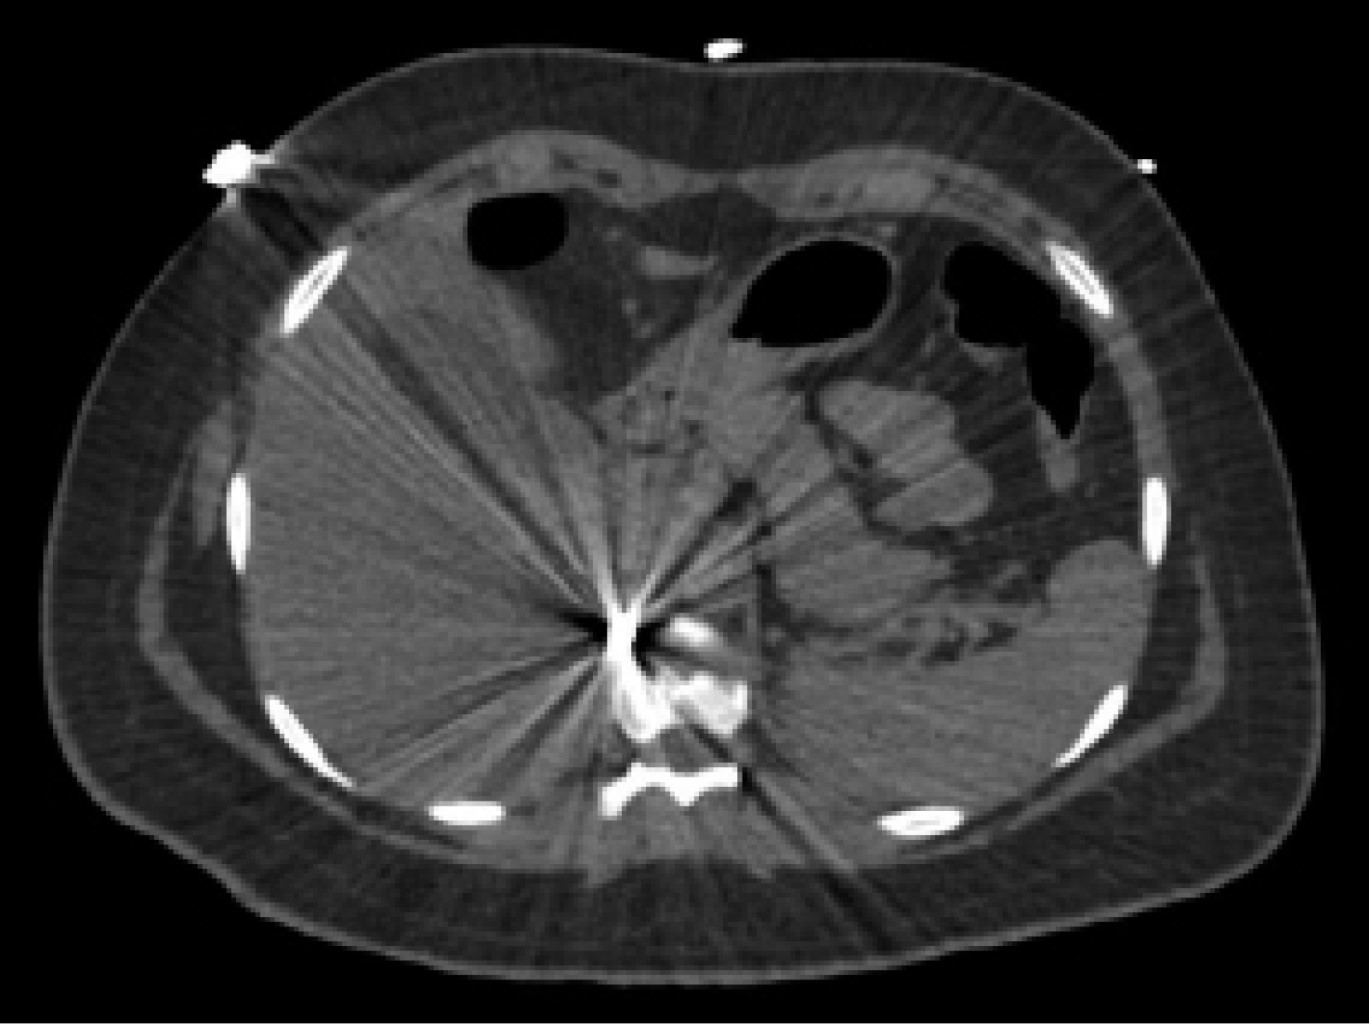

On physical examination, her vital signs were as follows: heart rate of 74 beats/minute; blood pressure of 98/67 mmHg; respiratory rate of 19/min; temperature of 36o C; and oxygen saturation of 98%. The chest showed a PAF entry orifice in the upper outer quadrant of the right breast (Figure 1), and the lung fields were well-ventilated. The abdomen was flat, with peristalsis, soft and painless to palpation. The blood cytology reported a hemoglobin of 12.8 g/dL, hematocrit of 36.4%, and white blood cells of 6,400/ml. The chest X-ray ruled out pneumothorax (Figure 2). A CT scan of the thorax and abdomen showed a metallic foreign body lodged in the right parasagittal line at the level of the 12th thoracic vertebra (Figure 3), without pulmonary or diaphragmatic lesion (Figures 4 and 5); in the abdomen, a PAF tract was observed with a 12 cm by 2.3 cm grade IV liver lesion in segments IV, VII and VIII of Couinaud (Figure 5), scarce free fluid, without lesion of any other organ (Figures 3, 5 and 6). Twenty-four hours later, a control CT scan was performed, showing the liver lesion without subcapsular collection or active extravasation on the application of contrast medium, without an increase of free fluid. Given the correlation of these findings with clinical stability, the patient was discharged on the fourth day of her admission. She did not have any complications one month after her discharge.

Figure 1